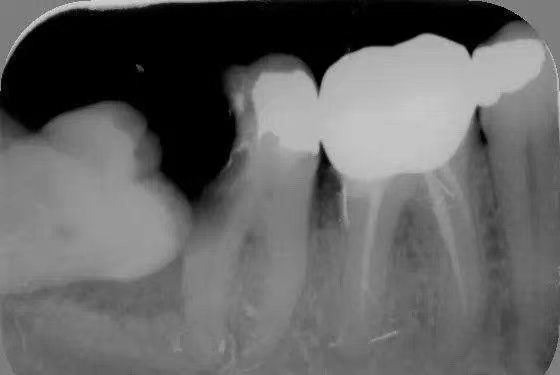

2.龋齿:阻生的智齿与第二磨牙之间容易积存食物残渣,而且不易清洁,很容易形成智齿和第二磨牙的龋齿而发生疼痛。

5.邻牙及支持组织的吸收:当阻生的智齿萌出过程中受阻于第二磨牙时,会引发第二磨牙牙根逐渐吸收,严重者可使下颌第二磨牙远中牙根完全吸收,致第二磨牙松动、疼痛。阻生智齿与第二磨牙间常食物嵌塞发生慢性牙周炎,也会造成牙槽骨的炎症性吸收,使第二磨牙反复肿痛。